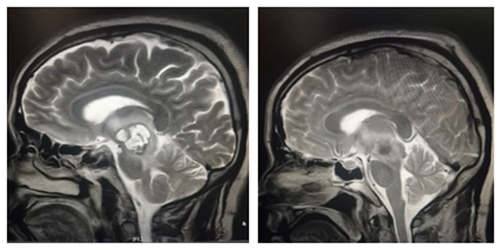

据了解,患儿小周今年11岁,因突发头痛呕吐、视物模糊前往医院就诊。到医院检查得知小周颅内松果体区长了一个鹌鹑蛋大小的肿瘤,并且已造成梗阻性脑积水,颅内高压,若不及时处理,随时有生命危险。医院神经外科王知非教授团队在接诊的首日就为患儿行急诊脑室外引流术缓解症状以便争取时间,随即为患儿制定手术方案。4月8日,王知非教授团队在全麻插管下为患儿行松果体肿瘤切除术,术后,患儿头痛呕吐视物不清等症状均好转,无任何功能障碍。

术前肿块影像                                                术后全切影像